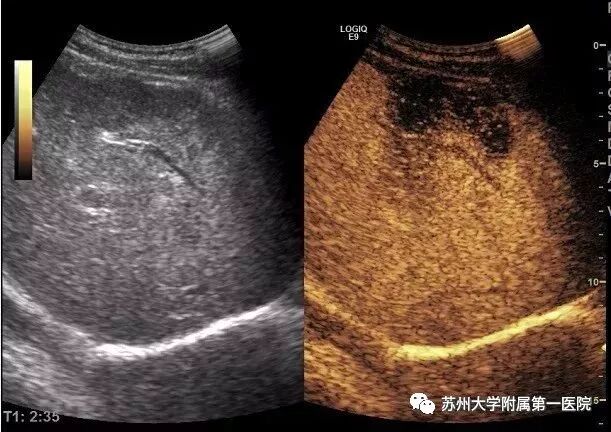

病例1

情况:患者男,57岁,右上腹隐痛5天,大便不成形4天”入院

外院CT提示脓肿可能,于我院就诊,准备行脓肿穿刺置管引流术,为术前明断诊断,先行超声造影检查,结果显示肿块呈不均匀低增强,延迟期造影剂消退,考虑肝K可能。行穿刺活检术,病理证实为:胆管细胞癌。

因超声造影可全程观察造影剂灌注与消退,信息完整,对病变的诊断特异性较高,在肿瘤良恶性的鉴别诊断方面效果显著。